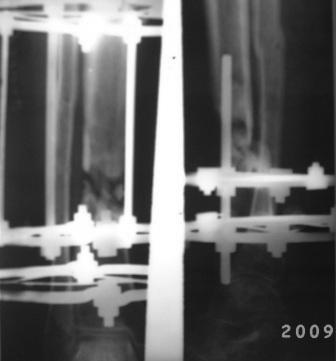

Обратился б-ной 39лет, ДТП 8-мес назад, о/оскольчатый перелом костей правой голени, в ЦРБ произведена ПХО раны, остеосинтез спицами и проволкой, гипсовая повязка, со слов б-ного рана зажило первично, гипсовая повязка переложена несколько раз, но сращения не наступило, 2 мес назад КДО аппаратом Илизарова, срашения нет, после обратился к нам.

Локально: признаков воспаления, лимфостаза нет, п/о рубец небольшой, сгибательная контрактура г/с сустава. Р-снимки прилагаются.

Наш план.1. Перемонтаж аппарата, устранение смещения, остеотомия в/з б/берцовой кости с постепенным низведением до полной компрессии в обл ложного сустава.

2. БИОС с рассверливанием к/м канала.